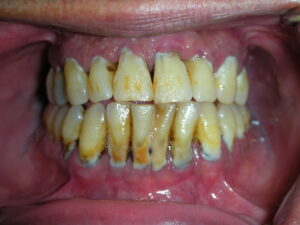

Periodontitis, pula, adalah bentuk keradangan gusi yang lebih serius dan berpotensi menyebabkan kehilangan tulang penyokong gigi. Selain daripada gusi yang bengkak dan bernanah, pesakit juga akan mengalami sakit yang tidak keterlaluan tetapi berterusan. Keadaan ini juga menyebabkan rasa tidak selesa ketika mengunyah makanan, bercakap, malah mengakibatkan bau mulut yang tidak menyenangkan. Nafas berbau dan rasa tidak selesa ini sebenarnya petanda awal bahawa penyakit gusi sedang berkembang ke tahap yang lebih serius.

Lebih membimbangkan lagi, jika rawatan tidak diambil segera, gigi akan mula bergoyang dan semakin bertambah goyang. Dalam kajian kebangsaan terbaru, dilaporkan bahawa sebanyak 38.2% penduduk Malaysia mengalami periodontitis iaitu penyakit gusi yang mampu merosakkan struktur sokongan gigi secara perlahan-lahan.